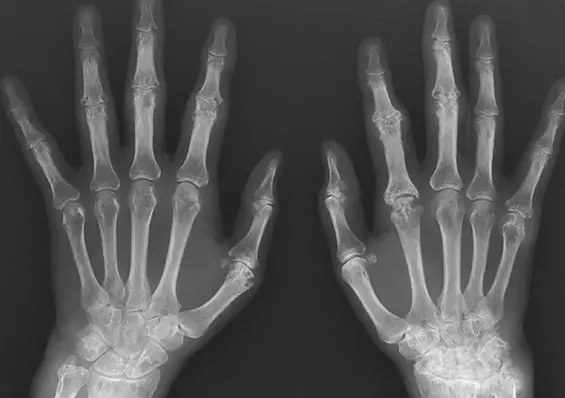

Diagnostyka różnicowa zespołów bólowych kończyny górnej. Część 1

Diagnostyka obrazowa